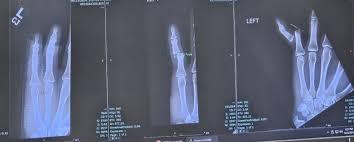

In the Dallas Cowboys’ dominant 44-22 victory over the Washington Commanders, Prescott delivered a near-flawless performance, throwing three touchdowns and leading the offense with full control. But what fans didn’t notice until after the game was the wrap on his left hand — a sign he’d been quietly playing through pain.

It wasn’t his throwing hand, but any injury to a quarterback’s hands raises alarm — especially from someone who once missed weeks with a fractured thumb. This time, though, there was no hesitation, no limitation, and definitely no backing down.